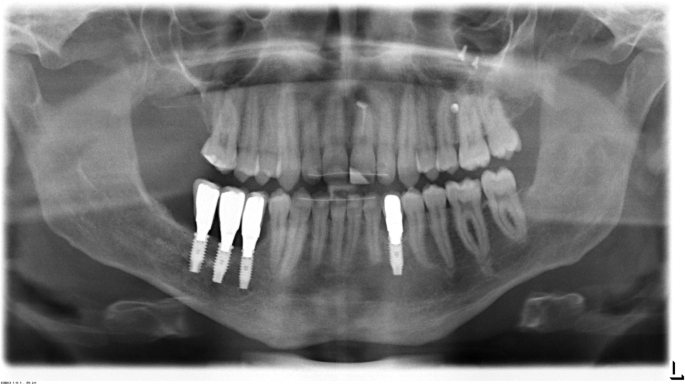

The orthopantomogram (OPT) showed a retention of the teeth 33 and 45 at the base of the mandible. In the peri-coronal area of both teeth enlarged radiolucencies with a clearly visible margin in region 33 and 45 were obvious. Additionally, in the area between teeth 46 and 47, a diffuse osteolysis confluent with a peri-coronar osteolysis around the retained 47 was visible. Furthermore, the teeth 35, 34 and 44 were angulated disto-mesially and root resorptions at the teeth 73 and 85 were observed. (Fig. 1).

Initial orthopantomogram (OPT) at the age of 11 years showing the extended pericoronar osteolyses of the teeth 33 and 45 which were retained at the base of the mandible. The adjacent teeth (32, 34, 44) seem to be dislocated by the cystic lesions. In the area between teeth 46 and 47, a diffuse osteolysis confluent with a peri-coronar osteolysis around the retained 47 is obvious. Furthermore, root resorptions at the teeth 73 and 85 are visible